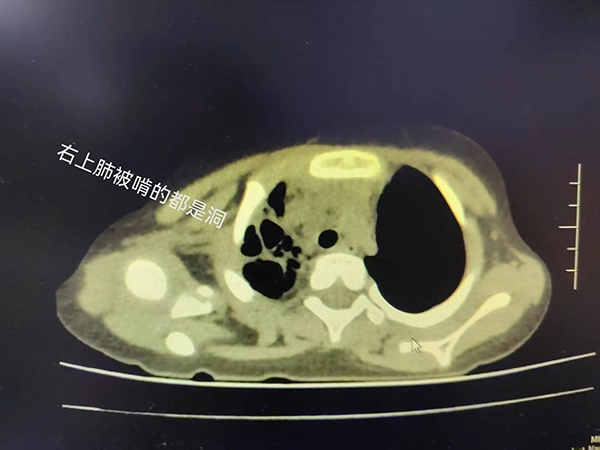

近日,我院小儿呼吸科收治了一名4岁小患者,他因持续高热、咳嗽10天入院。入院前虽经很多治疗,但病情仍逐渐加重,来诊时血常规显示白细胞高达2万(20×10⁹/L),炎症指标CRP 高达235.87mg/L,比正常值高出50多倍!胸片显示右肺炎,大约四分之三的右肺都被堵“没”了!我们立刻意识到这是一个特殊的重症肺炎!

入院后的胸部CT证实了我们的判断,病情不容乐观!热程已拖到10天,秉承着重症感染抗炎要重拳出击的原则,我们马上予以强有力的联合抗炎治疗,力求最快控制感染,并迅速安排了支气管镜术,在短时间内取得了病原结果,竟是“肺炎链球菌”这个经典的家伙!它的威力可不容小觑,只不过几天,小朋友的肺子就被啃成了“筛子”!

早期可见肺纹理增强或局限于一个节段的浅薄阴影,之后可能会出现大片状阴影,占全肺叶或一个节段。少数患者出现肺大疱或胸腔积液。个别肺炎链球菌肺炎出现化脓性并发症,可出现肺实变区的坏死病灶(看起来像是肺子成了筛网),或出现支气管肺胸膜瘘或大小不等的脓肿等。